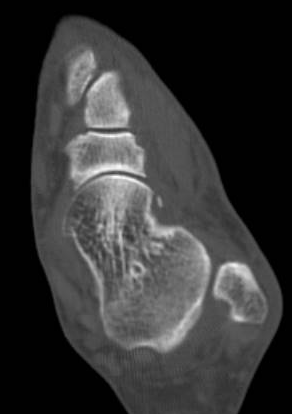

ÄÄÇ»ÅÍ ÃÔ¿µ : Á¾°ñÀÇ °ñÀý , µÎ ºÎÀ§(÷ºÎ ÆÄÀÏ Âü°í)

ÄÄÇ»ÅÍ ÃÔ¿µ ÆÇµ¶¿¡¼­ Á¾°ñÀÇ µÎ ºÎÀ§ °ß¿­°ñÀýÀÌ ¾ð±ÞµÇ¾úÁö¸¸ ÃÊÀ½ÆÄ°Ë»ç»ó  Ãß°¡ÀûÀÎ °ñÀýÀ»

È®ÀÎÇÒ ¼ö ÀÖ¾ú´Ù.

ÄÄÇ»ÅÍ ÃÔ¿­»óÀÇ °ñÀý ºÎÀ§´Â ÃÊÀ½ÆÄ°Ë»ç¿¡¼­ È®ÀÎÇÒ ¼ö ÀÖ¾ú°í »çÁø 10~15¿¡¼­ È®ÀÎÀÌ °¡´ÉÇÏ´Ù.